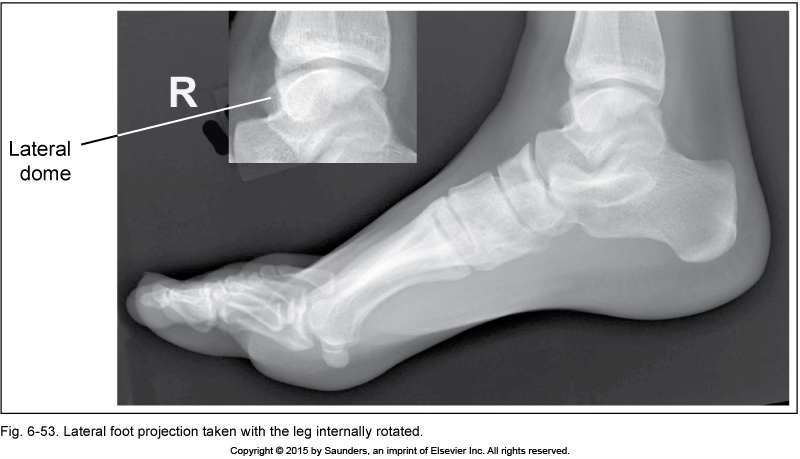

lateral foot

leg internally rotated

check fibula